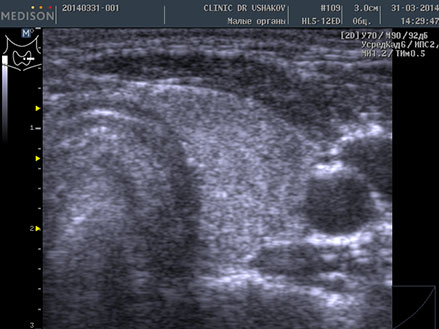

Пациентка К., 39 лет. При обследовании выявлены явления гипотиреоза и аутоиммунного тиреоидита. Через 1,5 года после лечебных мероприятий (в Клинике и соблюдение благоприятных условий) вместе с улучшением самочувствия произошло значительное восстановление щитовидной железы. В период лечения в связи с компенсированностью организма и гормонального обмена (Т4св. и Т3св.) и оздоровительным образом жизни медикаменты не применялись.

До лечения тиреоидита Анализ крови 9.06.2012 ТТГ 32 мЕд/л, Т4 св. 0,85 нг/дл АТ-ТПО 2113 ЕД/л | После лечения тиреоидита Анализ крови 15.01.2014 ТТГ 3,09 мЕд/л, Т4 св. 1,09 нг/дл АТ-ТПО 31,8 ЕД/л |

| В левой доле заметны: 1) значительно выраженная лимфоидная инфильтрация вдоль передней (вентральной) части доли и в перешейке ― признак аутоиммунного процесса, 2) единичные мелко- и среднеточечные очаги истощения и разрушения ткани. | В левой доле ткань восстановилась: 1) почти полностью исчезла значительная лимфоидная инфильтрация (заметна лишь очень мало выраженная гипоэхогенная зона у переднего края доли) ― устранение аутоиммунного процесса, 2) почти утилизировались очаги истощения, 3) восстановился объём |